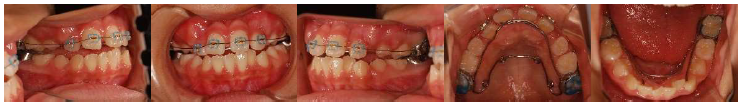

治療開始4か月後、上の大人の歯にワイヤーの装置を付けました。